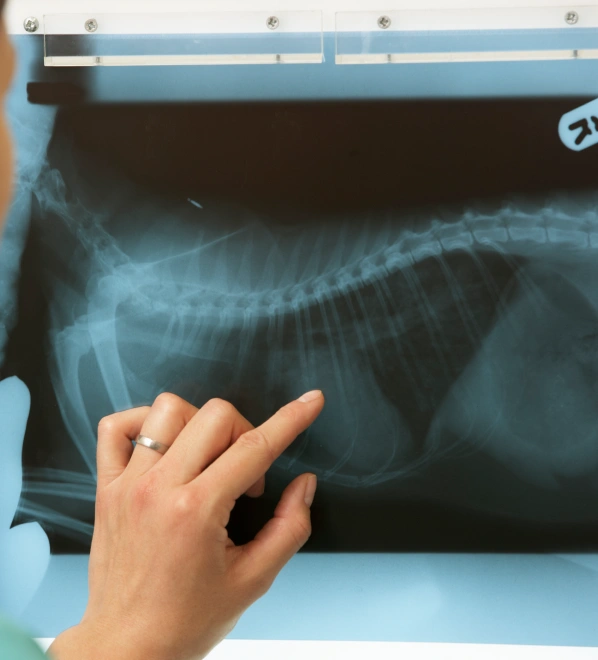

At Independence Veterinary Clinic, we understand that your dog’s health is a priority, and that’s why we use dog digital radiography in Charlotte to provide the most accurate and efficient diagnostic care available. Digital X-rays allow us to examine your dog’s bones, organs, and tissues in greater detail than traditional radiography, ensuring we catch potential issues early.

This non-invasive technology offers a quicker, more accurate way to detect injuries, diseases, or abnormalities. Whether it’s a routine check-up or an emergency, digital radiography service for dogs provides the clarity needed to develop an effective treatment plan for your dog’s health.

- Clearer, More Detailed Images: High-quality images allow us to assess your dog’s health with greater precision.